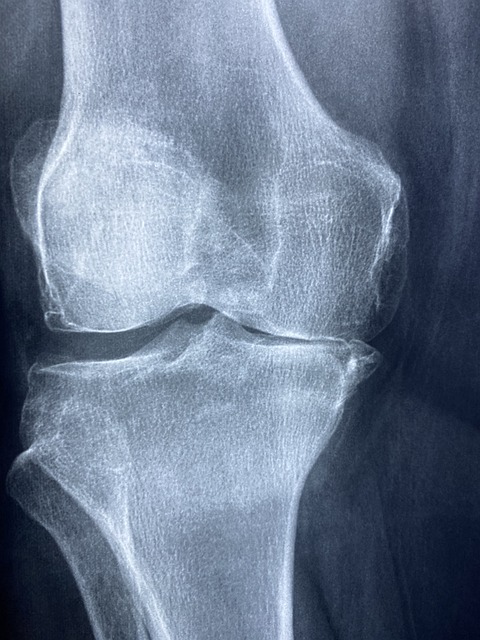

SBS 좋은아침 똑똑똑! 고민상담소 2024년 6월 6일: 산고와 맞먹는 통증! 퇴행성 관절염

SBS 좋은아침 똑똑똑! 고민상담소 2024년 6월 6일: 산고와 맞먹는 통증! 퇴행성 관절염으로 방송되었는데요! 퇴행성 관절염은 많은 사람들에게 심한 통증을 유발하는 만성 질환이에요. 특히 국내 45세 이상 인구에게 흔한 병이죠. 이 글에서는 퇴행성 관절염의 원인과 관리 방법에 대해 알아보겠습니다.

국내 45세 이상 만성 질환 1위 관절염

관절염은 45세 이상의 많은 사람들에게 영향을 미치는 만성 질환이에요. 특히 나이가 들수록 관절의 퇴행이 빨라져 더 많은 사람들이 이 질환으로 고통받고 있어요.

퇴행성 관절염은 어떤 증상이 있나요?

퇴행성 관절염의 주요 증상은 관절 통증, 부종, 강직함 등이 있어요. 특히 아침에 일어났을 때 관절이 뻣뻣한 느낌이 들 수 있어요.